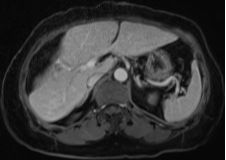

結腸腫瘤是指發(fā)生在結腸部位的腫瘤,可分為良性和惡性,結腸腫瘤早期癥狀不明顯,隨著病情發(fā)展,可能出現(xiàn)腹痛、便血、腸梗阻等癥狀,治療方法包括手術、化療、放療等,具體治療方案需根據(jù)患者的具體情況制定。